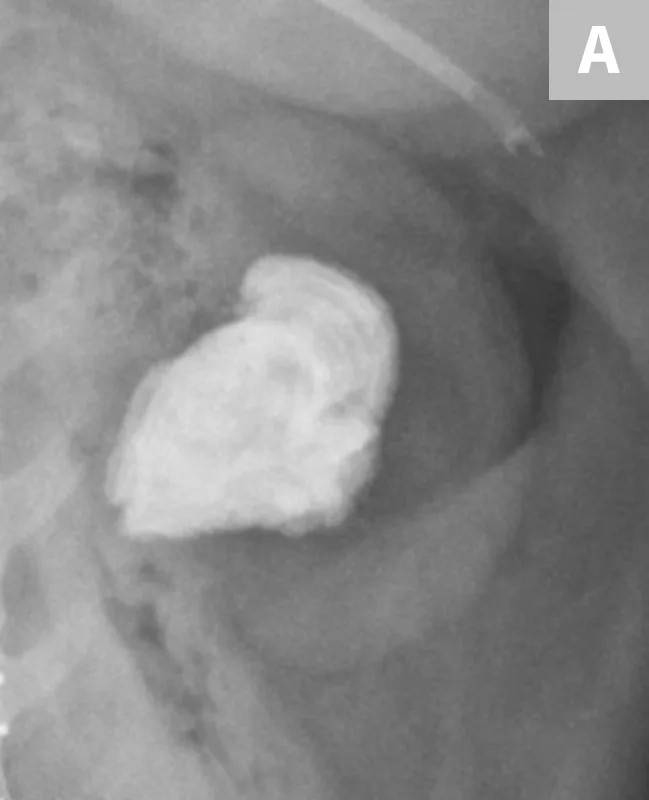

FIGURE 3A

Close-up radiograph of the left kidney with a large, smoothly margined renal calculus in a clinically normal canine patient.